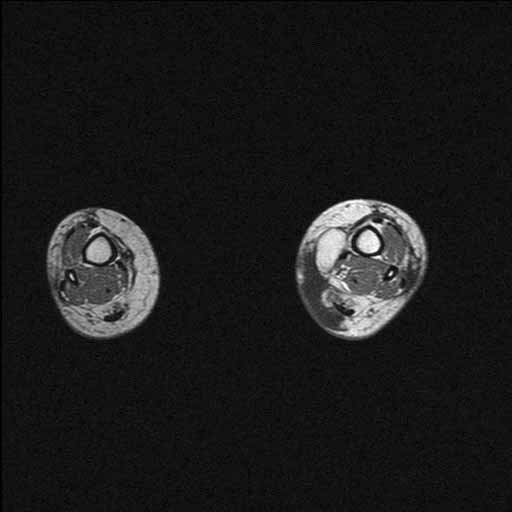

History:  The patient was a 44 year-old woman who complained of a 3 cm hard mass in her ankle at the medial aspect of her tibia. She had a mass that was removed from that area approximately about 3 years ago and the diagnosis was lipoma. She developed postoperative infection with a prolonged course and was treated. On physical examination, the mass was hard like a stone and was thought to be mineralized. MRI revealed fat density in the mass. The current mass was excised and yielded the this specimen.

MRI: There is an oval mass with fat density in the left ankle. The mass is very well demarcated from the surrounding tissue without evidence of invasion into the surrounding tissue.

MRI